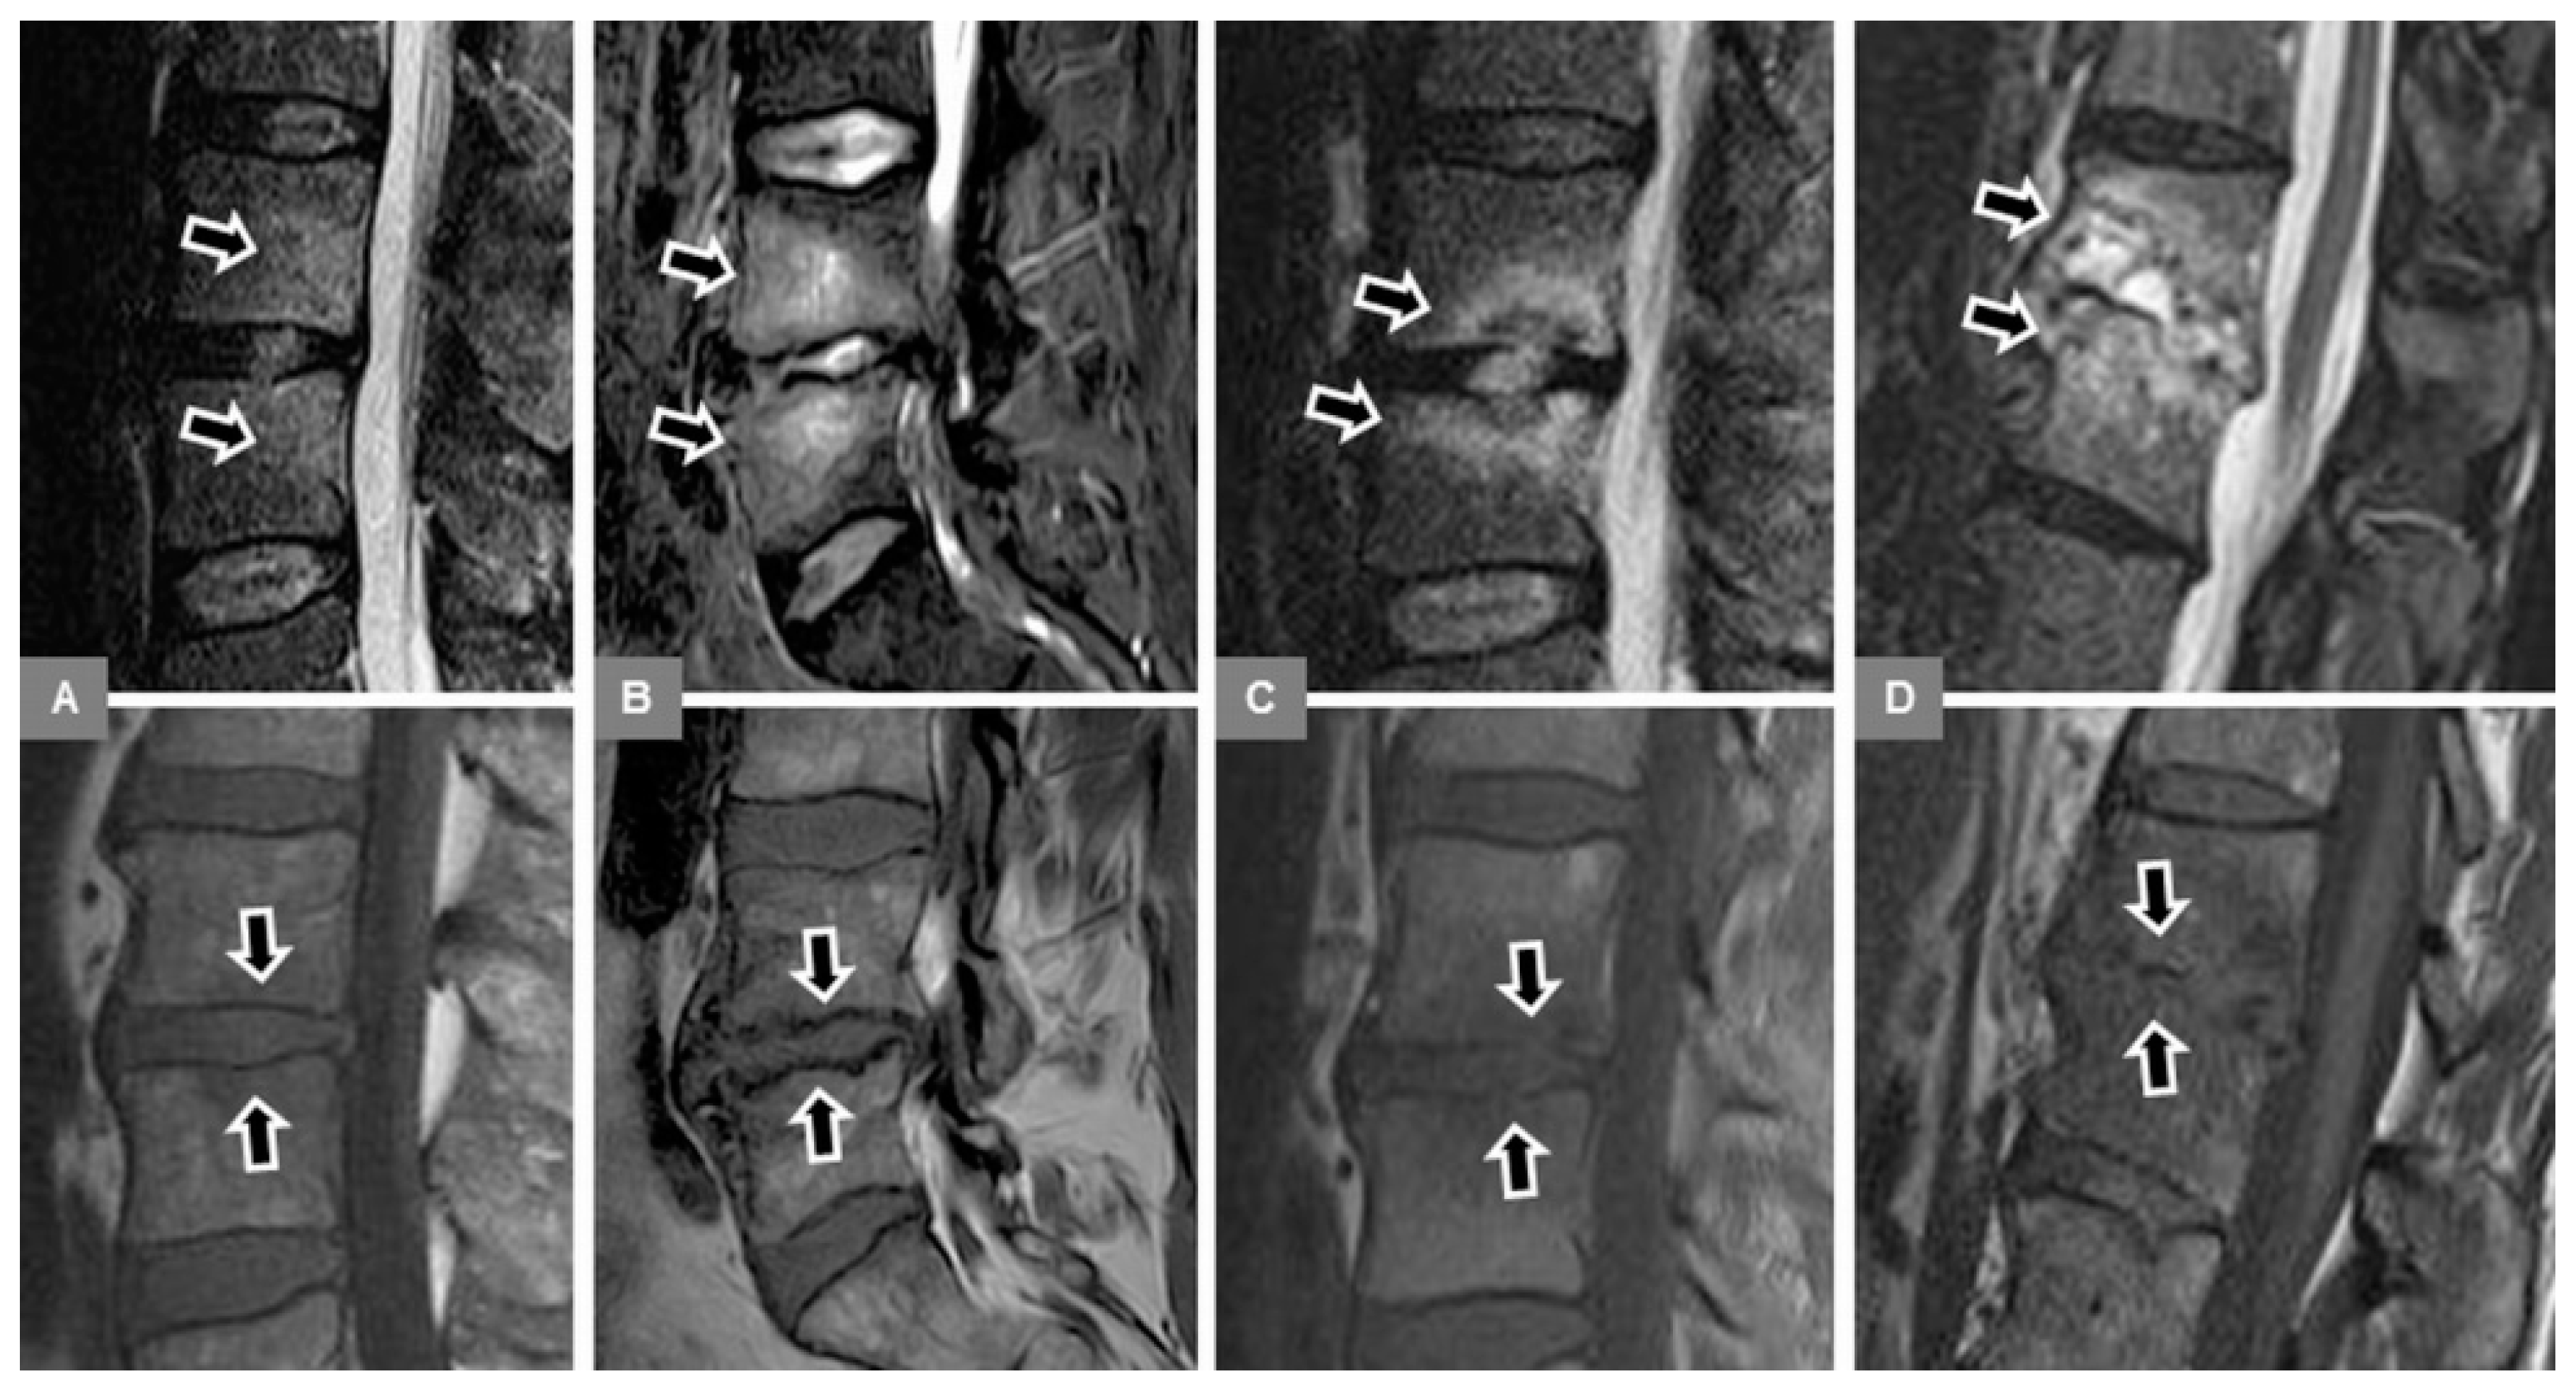

3.1. Bone Marrow Edema Extent, T1-w Signal Ratios of Edema to Unaffected Bone, and Visual T1-w Signal Assessment

3.2. Vertebral Endplate Contour

3.5. Appearance of the Intervertebral Disc

3.6. Modic Type 2 and 3 Endplate Changes